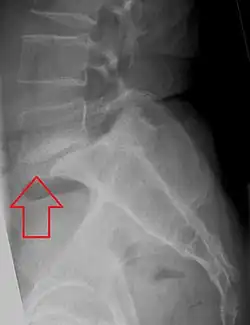

L5 S1 Spondylolisthesis Grade II with forward slipping of L5 on S1 <50% -

Forward displacement of a proximal vertebra in relation to its adjacent vertebra in association with an intact neural arch, and in the presence of degenerative changes, is known as degenerative spondylolisthesis,[9][10] which narrows the spinal canal, and symptoms of spinal stenosis are common. Of these, neural claudication is most common. Any forward slipping of one vertebra on another can cause spinal stenosis by narrowing the canal. If this forward slipping narrows the canal sufficiently, and impinges on the contents of the spinal column, it is spinal stenosis by definition. If associated symptoms of narrowing exist, the diagnosis of spinal stenosis is confirmed. With increasing age, the occurrence of degenerative spondylolisthesis becomes more common. The most common spondylolisthesis occurs with slipping of L4 on L5. Frymoyer showed that spondylolisthesis with canal stenosis is more common in diabetic women who have undergone oophorectomy (removal of ovaries). The cause of symptoms in the legs can be difficult to determine. A peripheral neuropathy secondary to diabetes can have the same symptoms as spinal stenosis.[11]